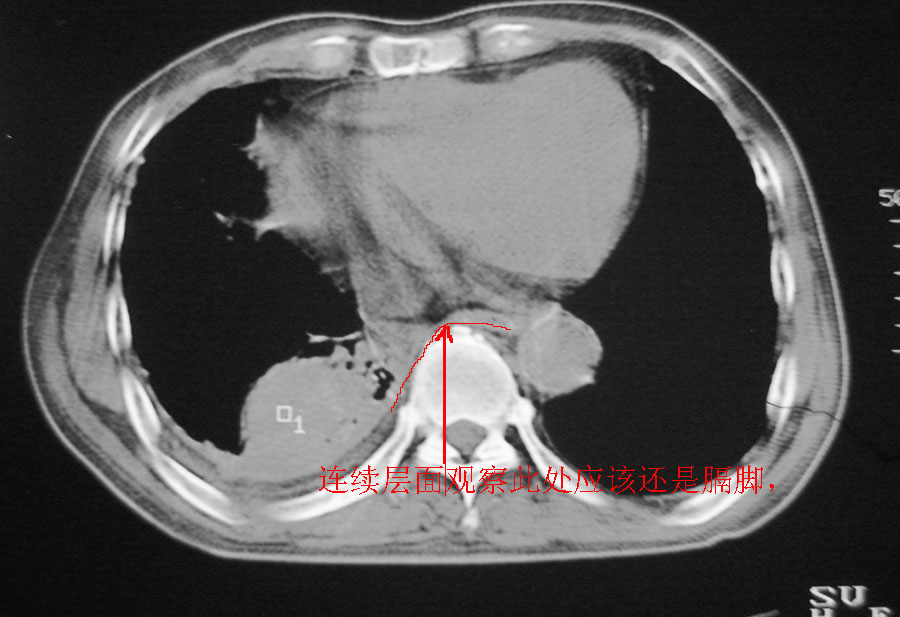

以下是引用天南地北在2007-1-24 18:00:00的发言:[br]1:右下肺内基底段类椭圆性肿快影:考虑1:右下球形肺炎2:右下肺隔离症,建议抗炎治疗后复查。[br]2:右肺及左下肺感染,右侧少量胸腔积液。